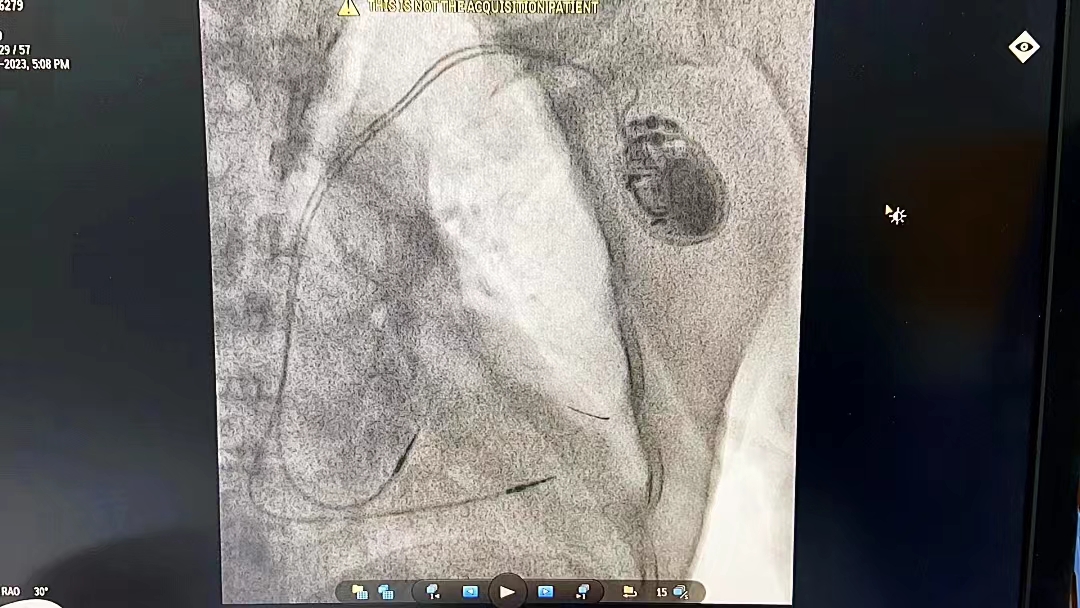

一切都按计划进行,2月8日,以刘旭阳副院长、王俊谊副主任为首的心内科介入团队顺利为患者植入了吉安市首例大容量长寿命抗高场核磁双腔起搏器,术中顺利,术后反映良好,起搏器工作各项参数正常。

在人均预期寿命不断延长的情况下,患者的年龄不算太老也不能算太年轻,却身患“病态窦房结综合征、脑梗死、帕金森综合征、颈椎间盘突出”四种疾病,我们既要解决他心脏停搏危及生命的问题,又要让他免受不必要的痛苦。因此,大容量长寿命抗高场核磁起搏器解决了朱大爷需频繁更换起搏器、不能做磁共振的烦恼。